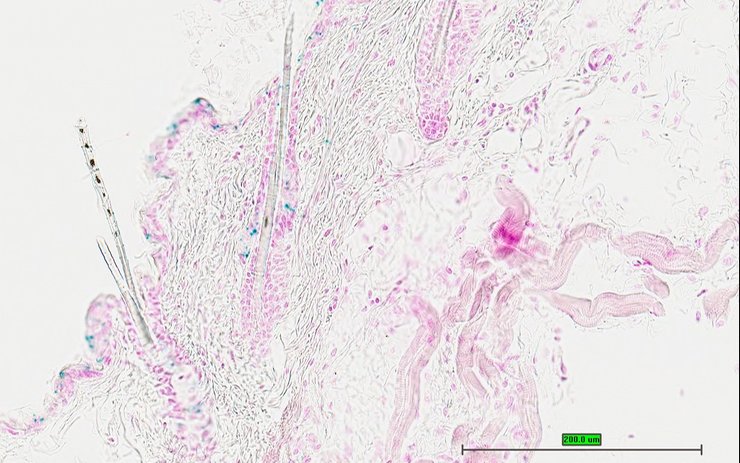

TS28: skin Present UC Davis_1884102

Specimen UC Davis_1884103: postnatal adult; Sumo1tm1.1(KOMP)Vlcg/Sumo1+ (more )

Structure Level Pattern Image Note

TS28: skin Present UC Davis_1884103